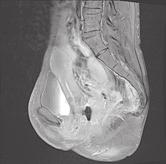

Pacientka narozená v roce 1988 trpěla od roku 2008 ulcerózní kolitidou s extenzivním postižením tlustého střeva. Od doby stanovení diagnózy byla léčena kombinovanou konvenční terapií mesalazinem, systémovými kortikoidy a imunosupresivy (azathioprin), aniž bylo dosaženo trvalejší remise. Pro chronicky aktivní průběh choroby byla ošetřujícím gastroenterologem indikována k provedení proktokolektomie s vytvořením ileopouch-anální anastomózy. Výkon byl proveden v roce 2016 otevřeným přístupem ve dvou dobách. V první fázi byla provedena proktokolektomie s formováním J pouche a ileopouch-anální anastomózy s pojistnou ileostomií v květnu 2016. Výkon byl komplikován traumatem stěny vaginy s nutností její sutury. V resekátu tlustého střeva byly zjištěny těžké zánětlivé a pozánětlivé změny, tubulizace lumen střeva a stenóza sigmatu v délce 20cm. V několika histologických řezech byly zachyceny shluky aktivovaných makrofágů, které byly hodnoceny jako mikrogranulomy. Pro přetrvávající subfebrilie a noční poty bylo koncem května 2016 provedeno CT vyšetření, při němž byla verifikována presakrální abscesová kolekce velikosti 55 × 45 mm. Následně byla provedena drenáž abscesu radiologicky pod CT kontrolou s velmi dobrým klinickým efektem.

S odstupem několika měsíců byla v září 2016 zrušena pojistná ileostomie a obnovena střevní kontinuita. Po stabilizaci stavu měla pacientka 5–8 stolic denně, měla intermitentní bolesti v podbřišku, vyprazdňovala střevní obsah z pouche bez hnisu, krve nebo hlenu, v noci byla zpravidla 1–2krát probuzena pro potřebu vyprázdnění střevního obsahu. Celkově se cítila velmi unavená, občasně měla zvýšené teploty a noční poty. Užívala intermitentně topické i systémové kortikosteroidy, mesalazin a opakovaně metronidazol, celkově a lokálně v podobě čípků. Několikrát byla provedena endoskopie ileálního J-pouche, při kterých byl zjištěn nález ojedinělých a spíše povrchových vředů, vždy v distální části pouche nad vytvořenou pouch-anální anastomózou. V průběhu dalších ně-

kolika let postupně ztrácela na tělesné hmotnosti. Mezi lety 2017 a 2024 zhubla celkem o 12kg, nejnižší hmotnost měla v první polovině roku 2024, a to 37 kg (BMI = 16). V červenci 2024 byla provedena pouchoskopie s překvapujícím nálezem píštěle lokalizované cca 35 mm nad ileopouch-anální anastomózou na zadní cirkumferenci, o průměru cca 3–4mm (viz video, které naleznete na webu www.csgh.info). Následně byla doplněna MR malé pánve (obrázky). Jaká je vaše diagnóza? A jaký bude další terapeutický postup?

Otázka:

Jaká je Vaše diagnóza? Správnou odpov a komentá naleznete v p íštím ísle.